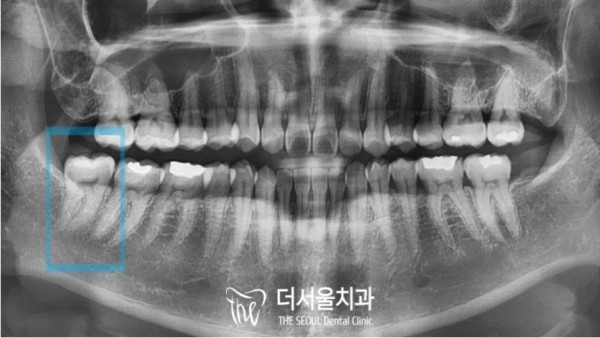

파노라마 엑스레이로 보았을때에는 신경관과

사랑니 뿌리가 아주 가까워 보이는것이 문제인 상황입니다.

저 신경을 잘못건드리면 안면마비, 신경손상... 아주 큰 부작용이 생길 수 있습니다.

Panorama X-ray shows that the neural tube and

The problem is that the wisdom tooth roots look very close.

If you touch those nerves incorrectly, you can have very big side effects, like facial paralysis, nerve damage.